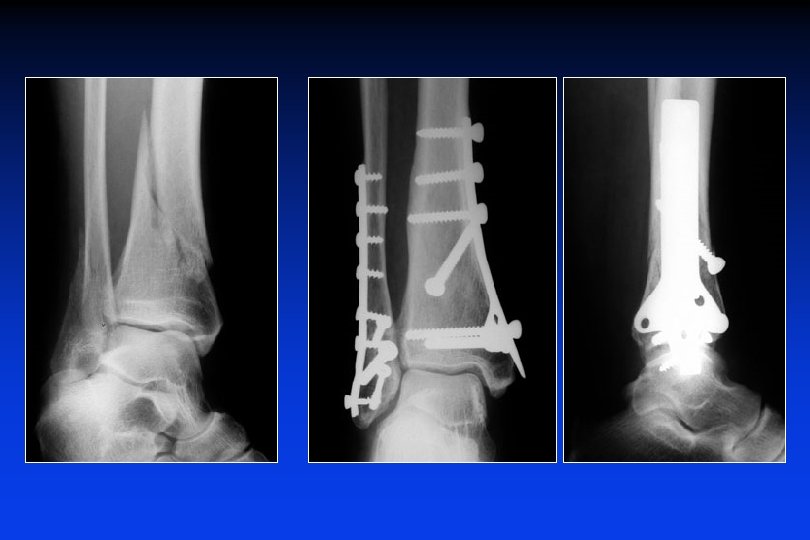

Trattamento delle fratture trimalleolari Fratture scomposte : Osteosintesi a qualsiasi età

Fratture del pilone tibiale + malleoli Osteosintesi : 1 placca sul malleolo esterno, 1 vite sul malleolo interno e 3 viti di richiamo sul frammento posteriore

Trattamento delle fratture del pilone tibiale • Sintesi anatomica del perone (ristabilire la lunghezza) • Ricostruire la superfice articolare (fili + viti) • Placca sulla superfice interna della tibia